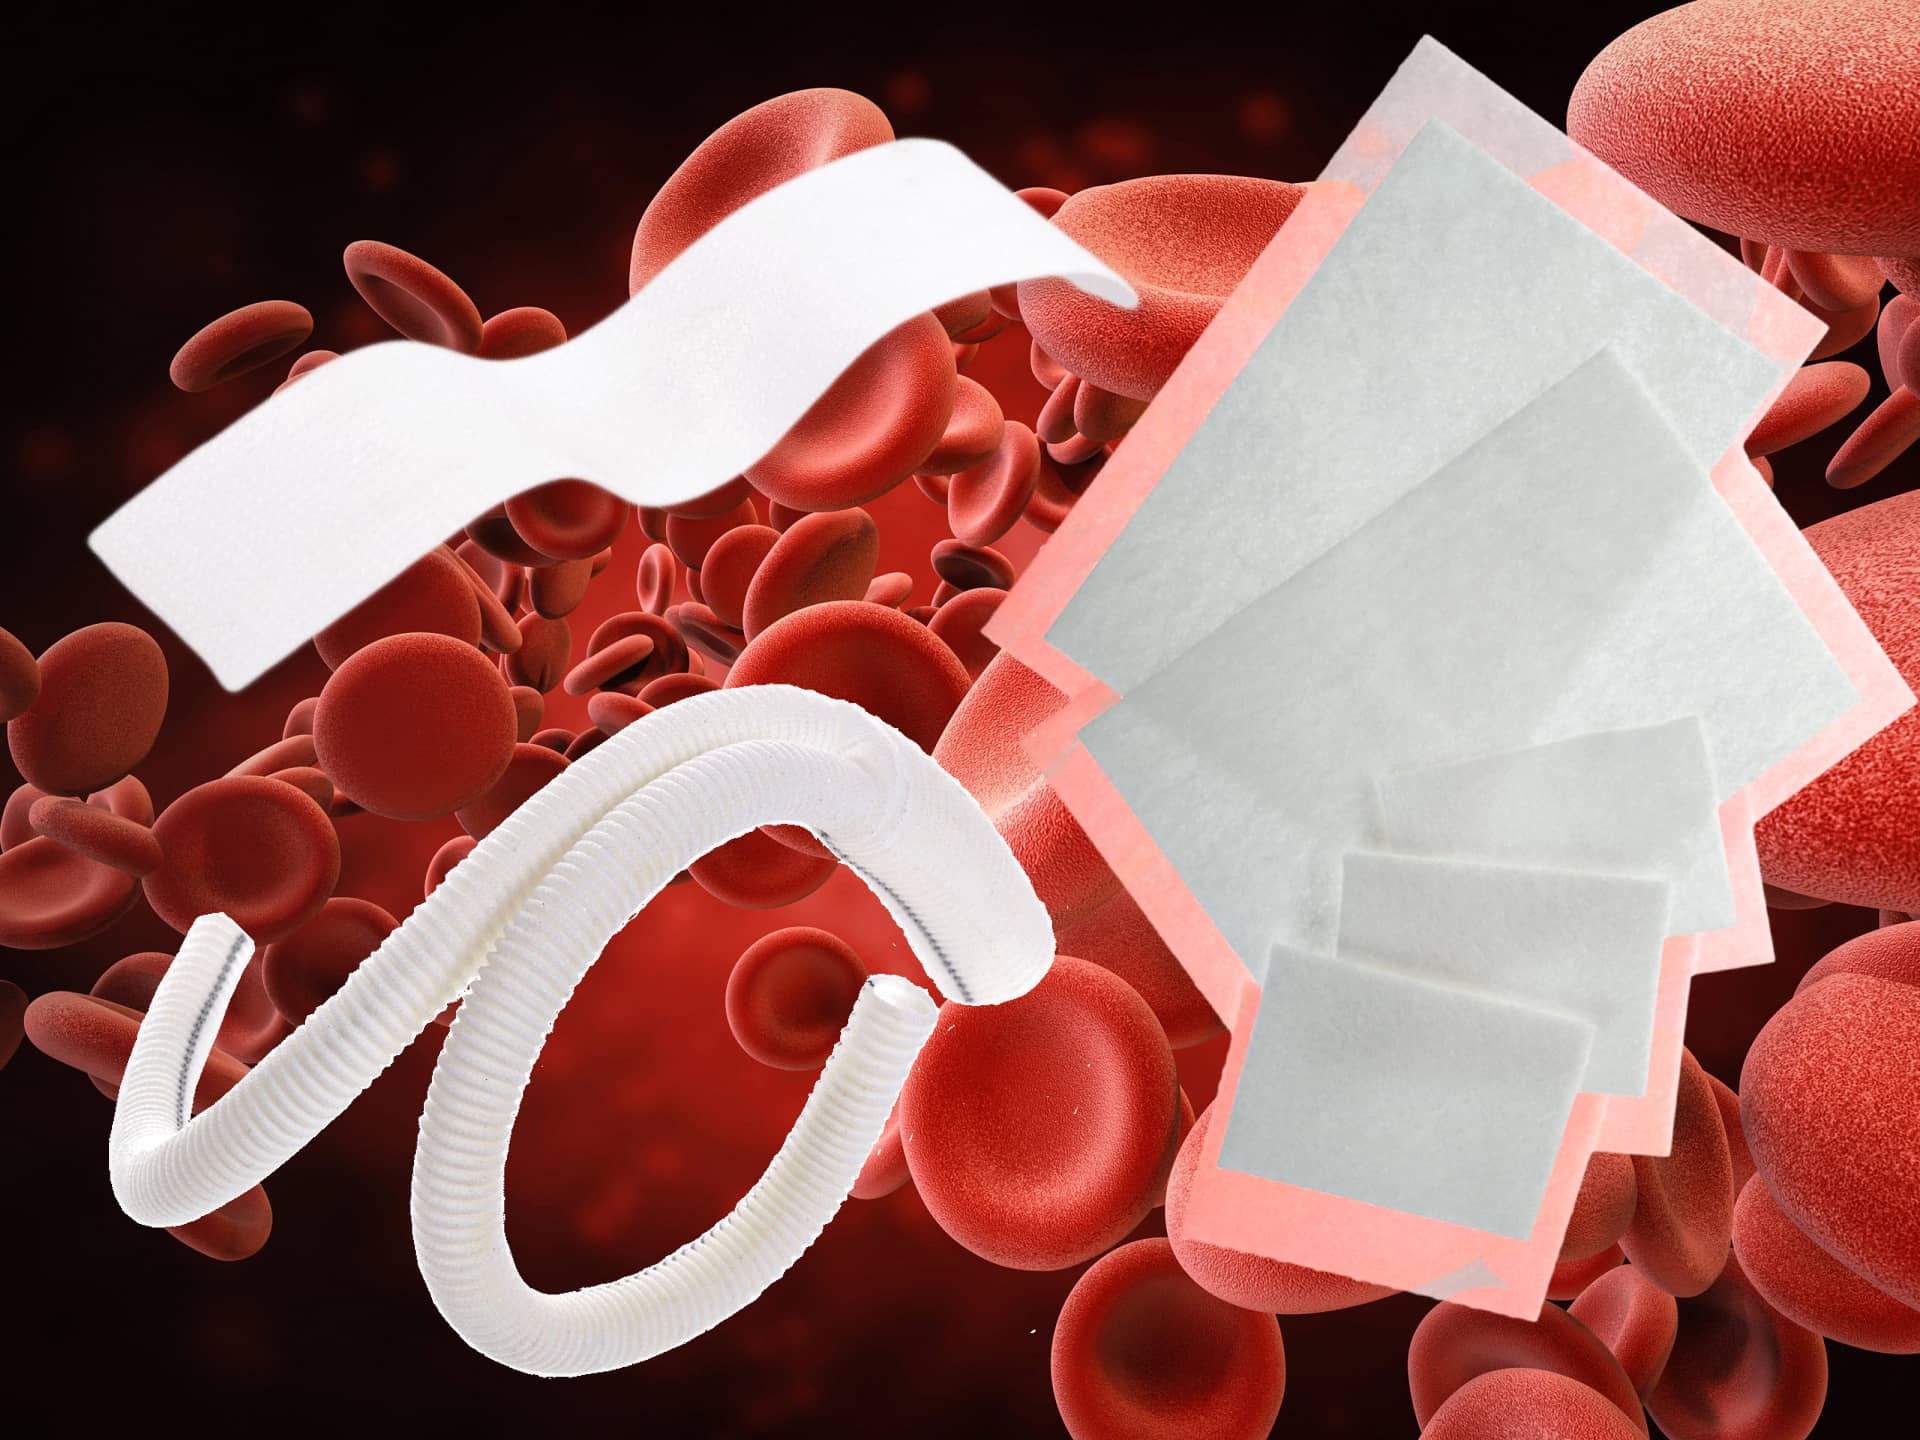

Thrombosis is a serious condition where one or more blood clots form in your blood vessels or heart. When this happens, the clot can block blood flow where it formed, or it can break loose and travel elsewhere in your body. If a moving clot gets stuck in a critical area, it can cause life-threatening conditions like stroke and heart attack.